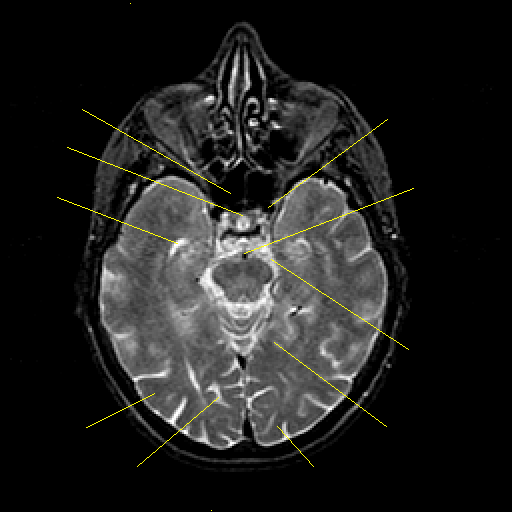

T2-weighted structural MR: Slice 20

Slice 20

Pointers

Labeled